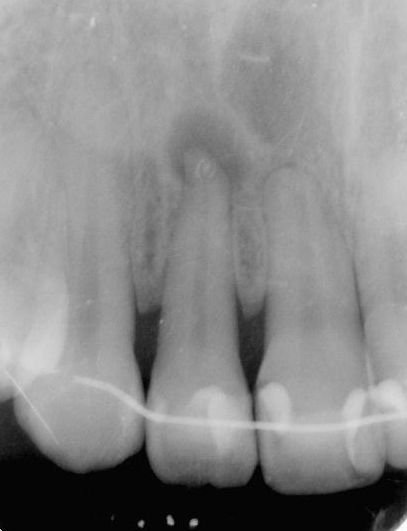

図1a 上顎側切歯の根尖病変. 根尖部にレントゲン透過像(黒い影)が見られる